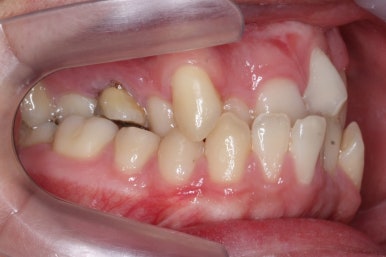

위아랫니가 각각 가지런해지고 있는 것을 볼 수 있습니다.

윗니는 아직 가지런하게 하는 작업 중이며, 아랫니는 가지런하게 하는 작업은 거의 다 되었습니다.

계속 윗니는 가지런히 해주고 있으며 아랫니는 앞뒤를 뒤로 당기고 있습니다.

거꾸로 물리던 앞니가 서서히 개선되어 가는 것을 볼 수 있습니다.

부산구순구개열 키다리아저씨치과에서 교정치료 하신지 1년여만에 드디어 앞니는 거꾸로 넘어왔고, 윗니들도 상당히 많이 가지런해졌습니다.

이 뽑은 자리도 상당히 많이 줄어든 것을 볼 수 있고, 이제는 정상적인 포개짐이 만들어졌습니다.